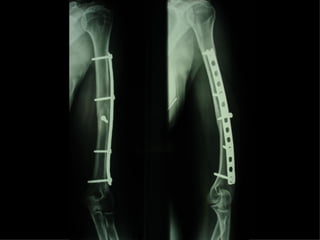

Dal Gennaio 2000 al Febbraio 2006 abbiamo trattato 167 fratture chiuse  con placca percutanea  in 164 pazienti :  27 lesioni diafisarie di gamba, 12 piloni tibiali ,  11 fratture prossimali di tibia, 36 fratture sovracondiloidee di femore, 17 fratture diafisarie di femore, 43 fratture metaepifisarie prossimali di omero, 21 diafisarie d’omero.  156 guarigioni 8 fallimenti

Dal Giugno 2002 al Dicembre 2004 abbiamo trattato 5 fratture esposte: 3 di tibia e 2 di ulna 5 guarigioni

I buoni risultati ottenuti dipendono da 5 punti fondamentali:   una accurata riduzione percutanea della frattura  precise vie di accesso  l’utilizzo della placca che consenta il più lungo braccio di leva possibile il pretensionamento della placca  una sintesi con un ridotto numero di viti

Placche lunghe e pretensionate

Placche lunghe e pretensionate Sintesi con un ridotto numero di viti

Fratture  esposte

Dal Gennaio 2000 al Dicembre 2005 27 placche LISS di femore

VANTAGGI CHIRURGIA MININVASIVA Mini Open Inserimento della placca sottocutaneo per scivolamento Viti percutanee Preservazione dei tessuti molli Ridotto danno vascolare Rapida ripresa funzionale